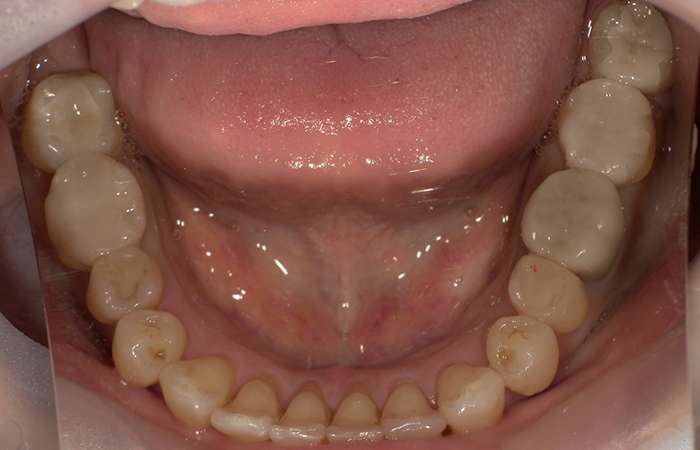

治療後 ![]() |

破折およびう蝕部分を適切に除去した後、金属を使用しないジルコニアインレーによる修復を行いました。咬合力を考慮しながら、歯への負担を最小限に抑え、審美性・強度・生体親和性のすべてを重視した治療計画としました。また、矯正治療も行いました。 |

術後は噛み合わせ時の違和感も改善し、自然な見た目で口元を気にせず過ごしていただけるようになりました。金属を使用していないため、金属アレルギーの不安も解消されています。 |